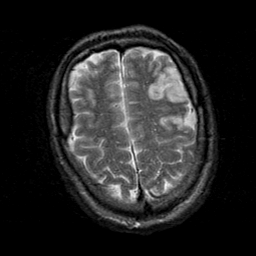

Subacute Stroke, overlay -- Slice #20

[Home][Help][Clinical] Slice 20